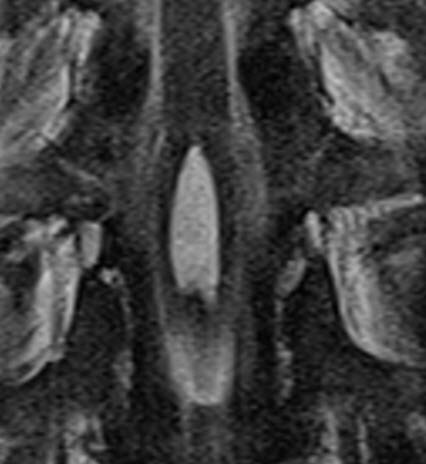

Axial T1 weighted MRI showing the cystic lesion adherent to the dura.

Coronal T2 weighted MRI showing the cystic lesion inside the conus medullaris.